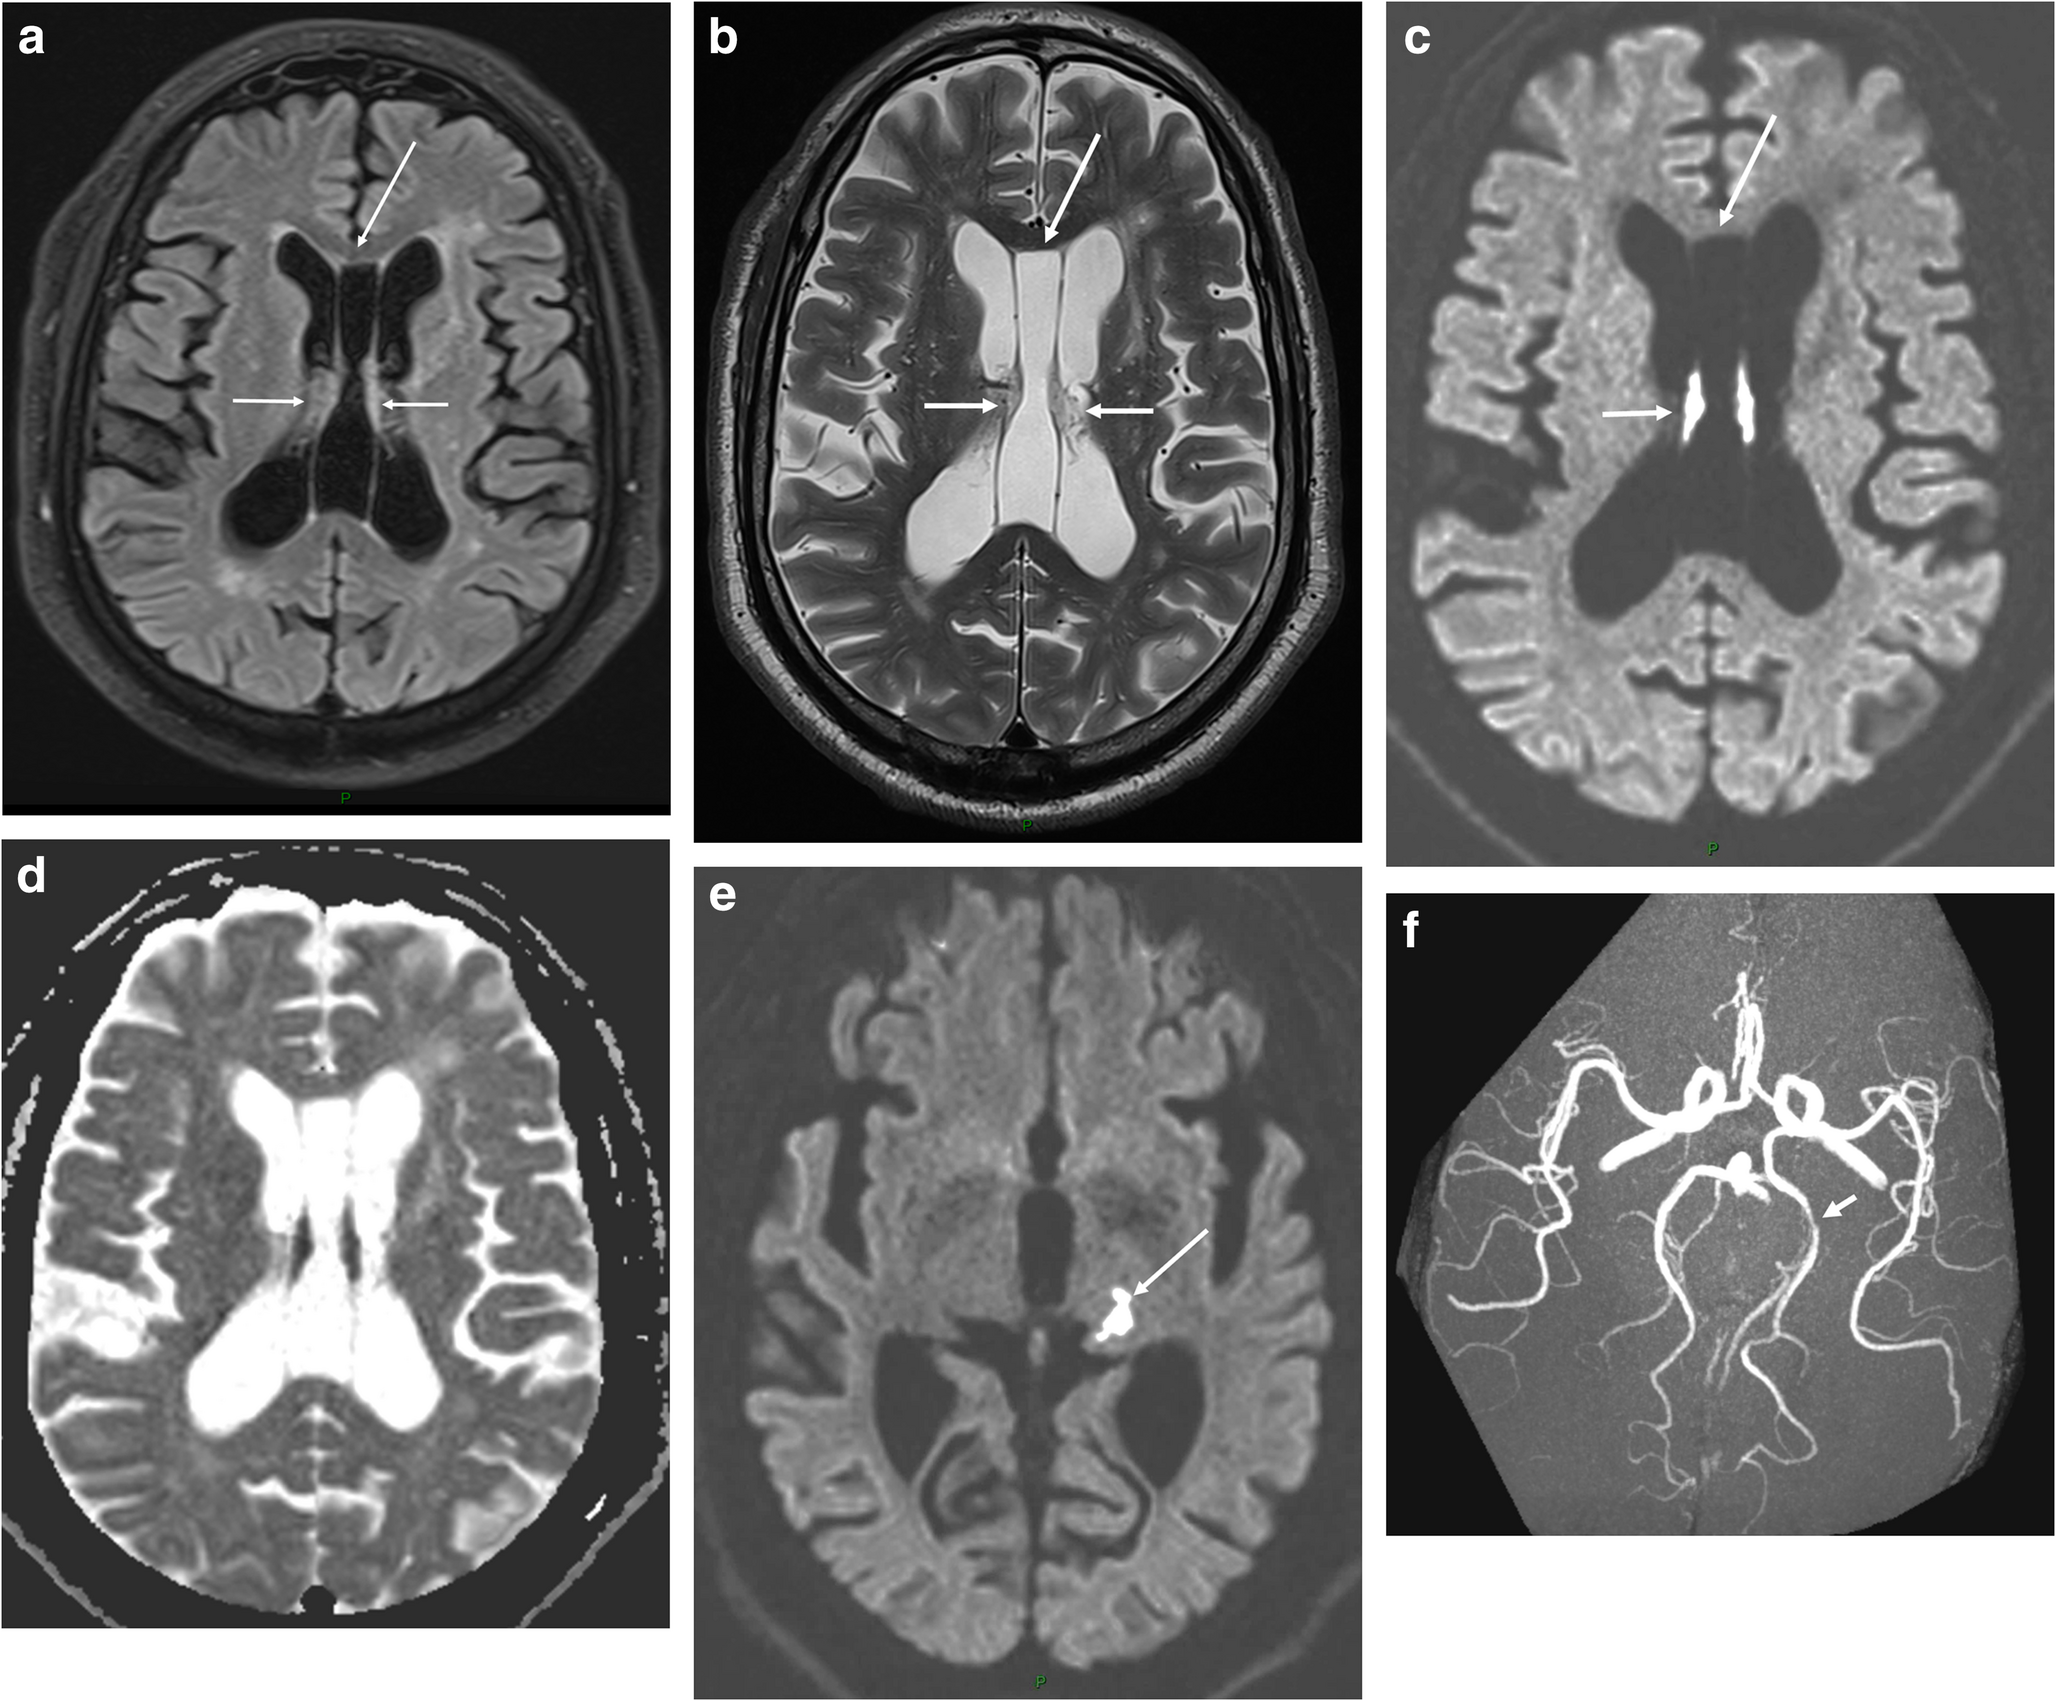

Purpose: Bilateral damage of fornix bodies has been reported in a few cases of brain tumors and in exceptional cases of ischemia. Methods: a 73-year-old man presented with acute right ataxic hemiparesis and right hypoesthesia. Brain MRI showed an acute ischemia of both fornix bodies and of the left posterior lateral thalamus, along with a septum pellucidum (SP) cyst. MR angiography revealed a 7-mm long stenosis of the initial P2 of the left posterior cerebral artery. Neuropsychological evaluation documented an amnestic syndrome. Fornix bodies and posterolateral thalamus are supplied by the medial and lateral branches of posterior choroidal artery, arising from the initial P2. As our patient presented a single intracranial vascular lesion on MR-angiography, i.e. long stenosis at the initial P2, left thalamic ischemia and ischemic lesions of both fornix bodies were due to the unpaired variation of that artery. Moreover, this fornix ischemia occurred in association with SP cyst, which did not favored the ischemia, but resulted in a unique and unreported pattern, because of the configuration and relationships of the fornix. The amnestic syndrome related to the fornix ischemia in our patient was non-specific. Conclusions: unreported condition of infarct of both the fornix bodies- responsible for acute anterograde amnesia- and of left inferolateral and posterior thalamic territories, related to an atheromatous stenosis of the initial left P2 posterior cerebral artery. The fornix bodies infarct occurred in a patient with a large SP cyst, which gives a particular pattern, non-previously described.